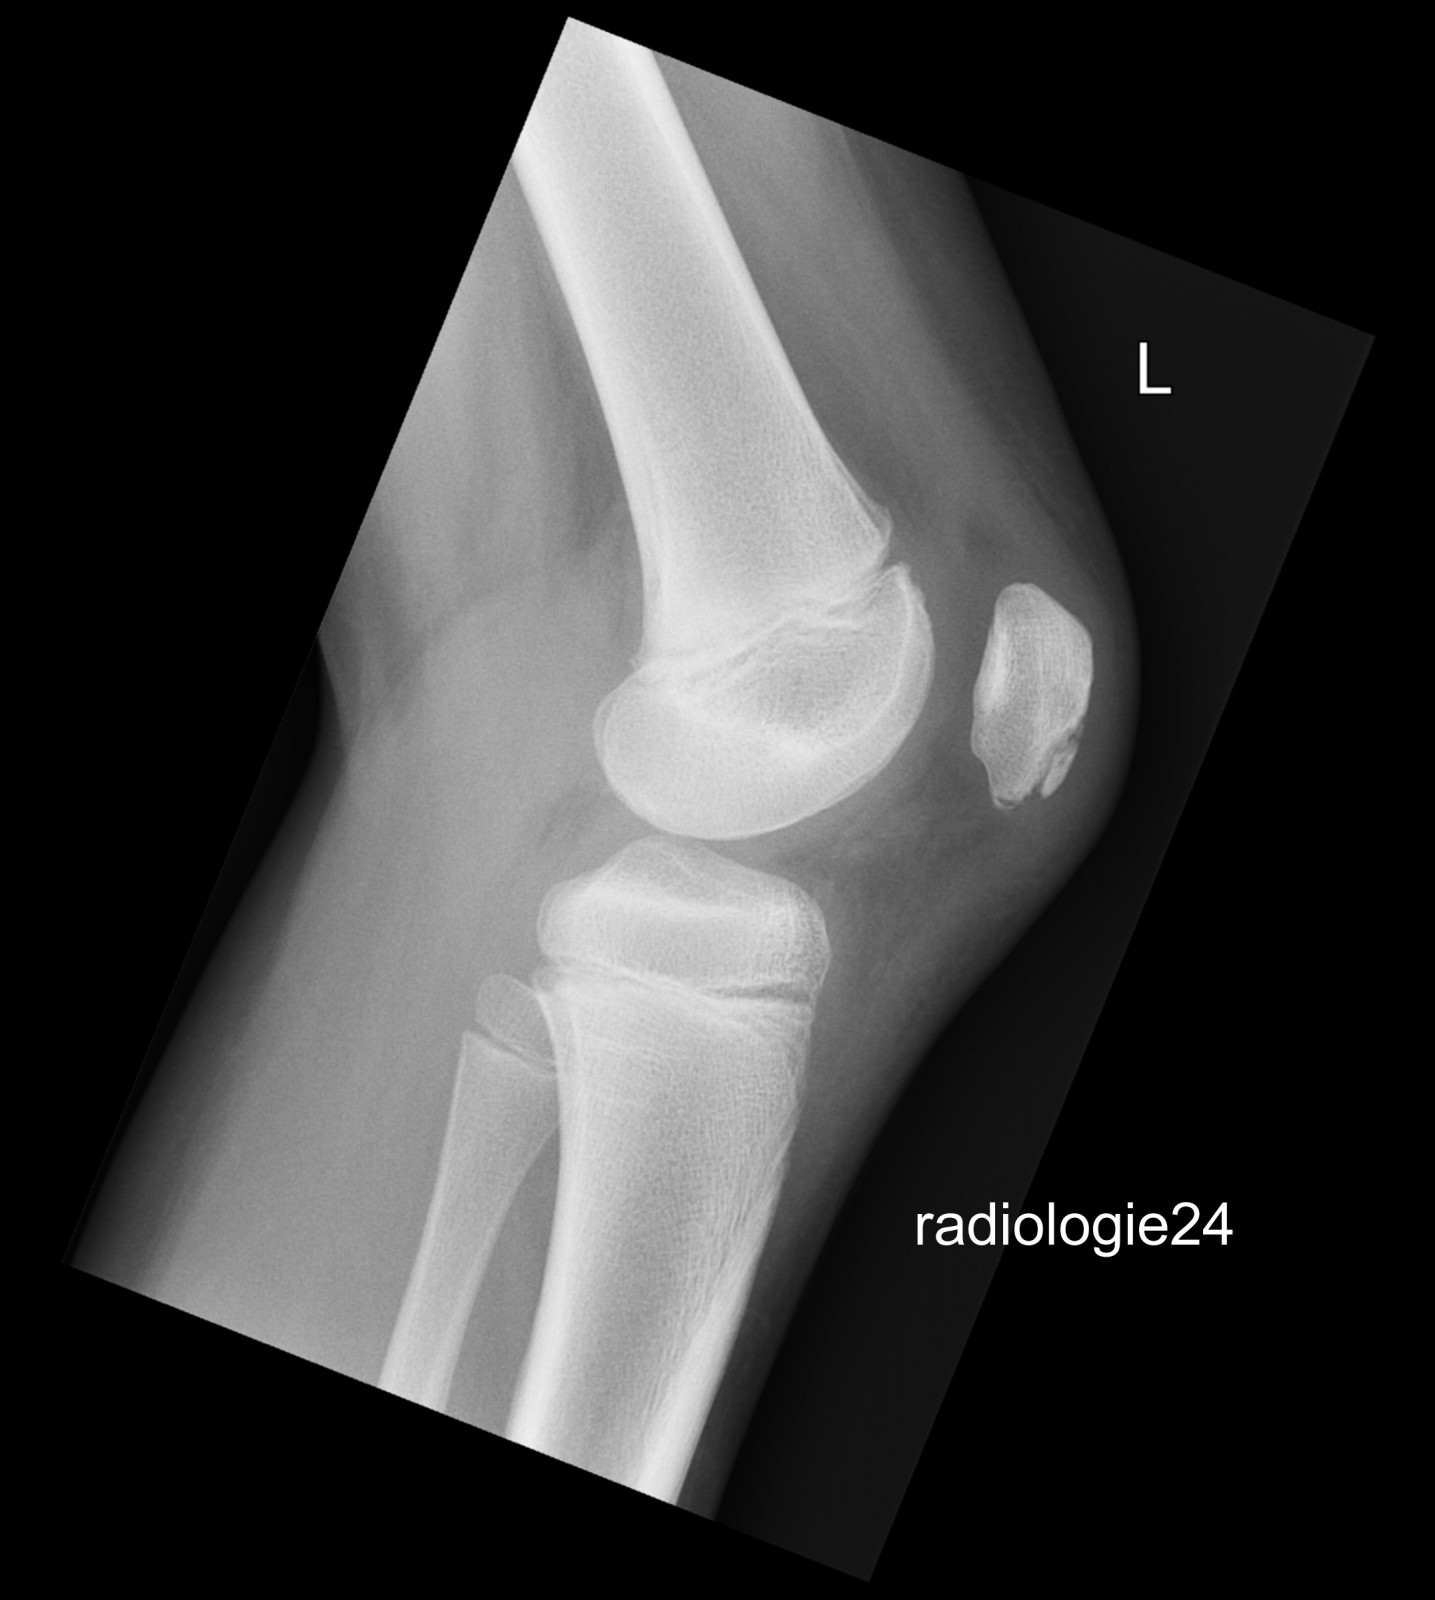

Röntgenfall des Monats März 2018 mit Auflösung

10 jähriger Patient Z.n.Sturz. Schmerzen im Bereich des Kniegelenks Ihre Diagnose?